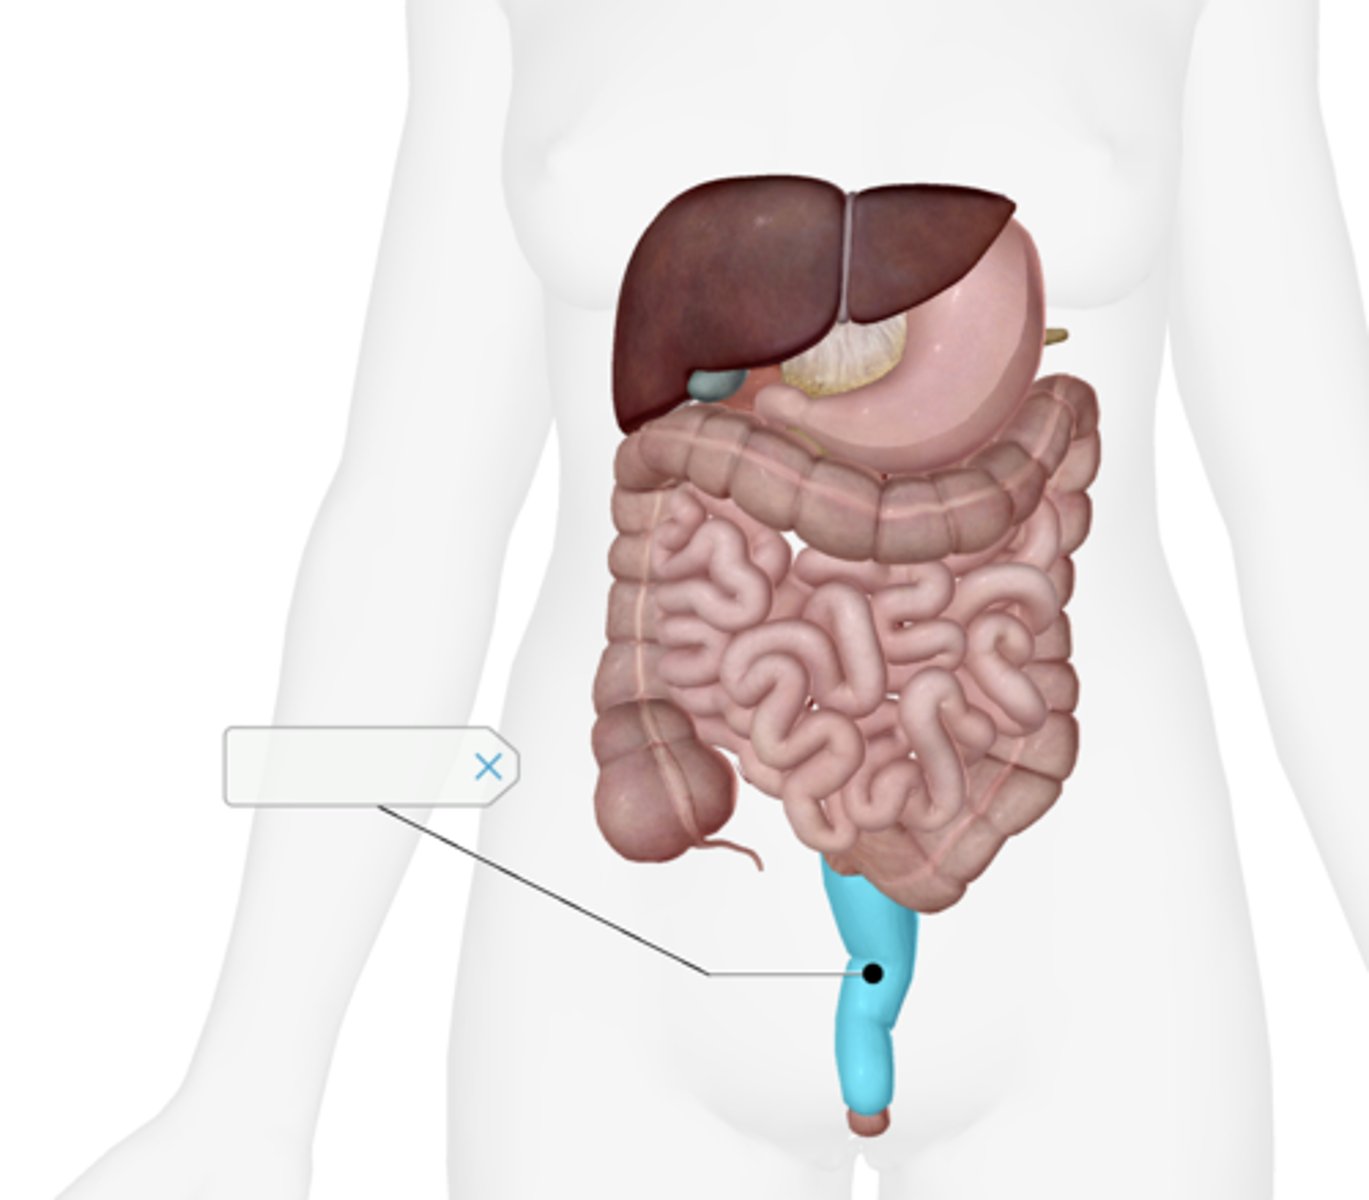

Appendix

Rectum

Anal canal